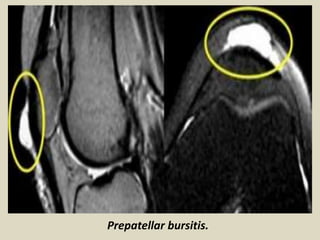

Prepatellar bursitis. A 44-year-old female presented with anterior knee pain. Axial (A) and

coronal (B) T2W fat saturated images showing a distended pre patellar bursa (arrows)

Prepatellar bursitis.